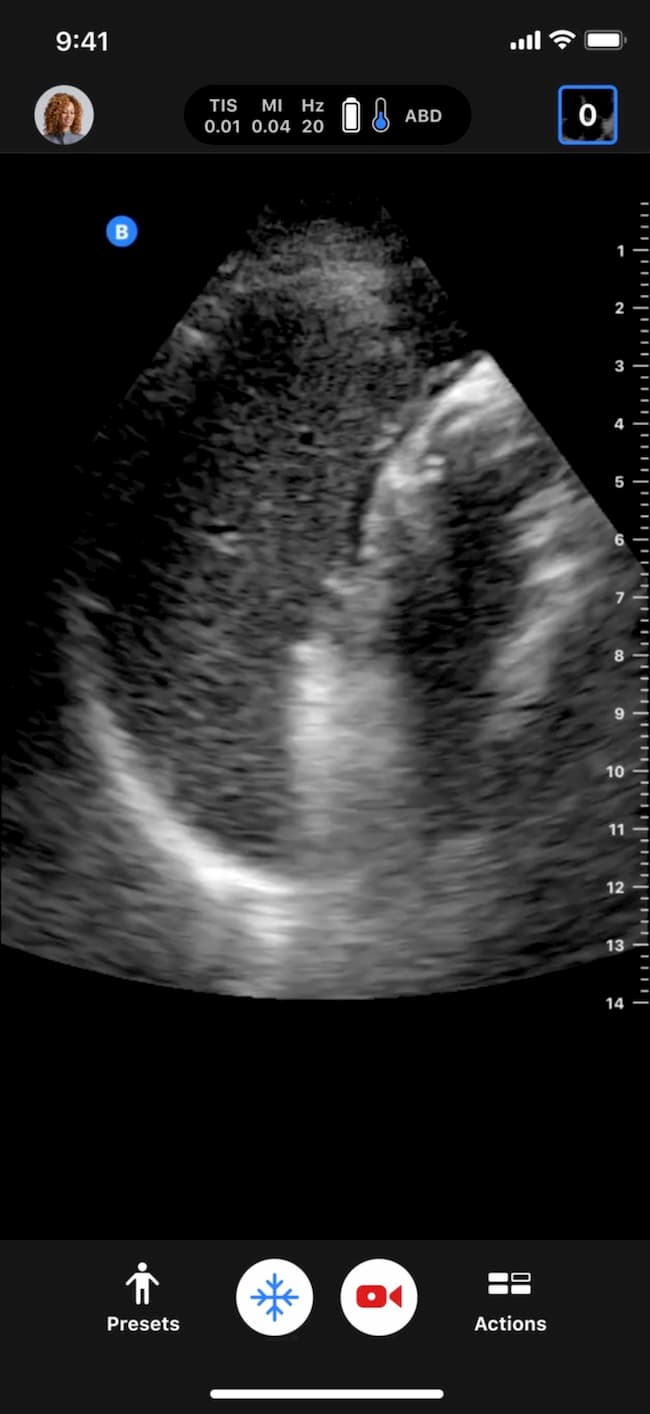

Cardiac

Cardiac Biplane PLAX PSAX

Clinical gallery